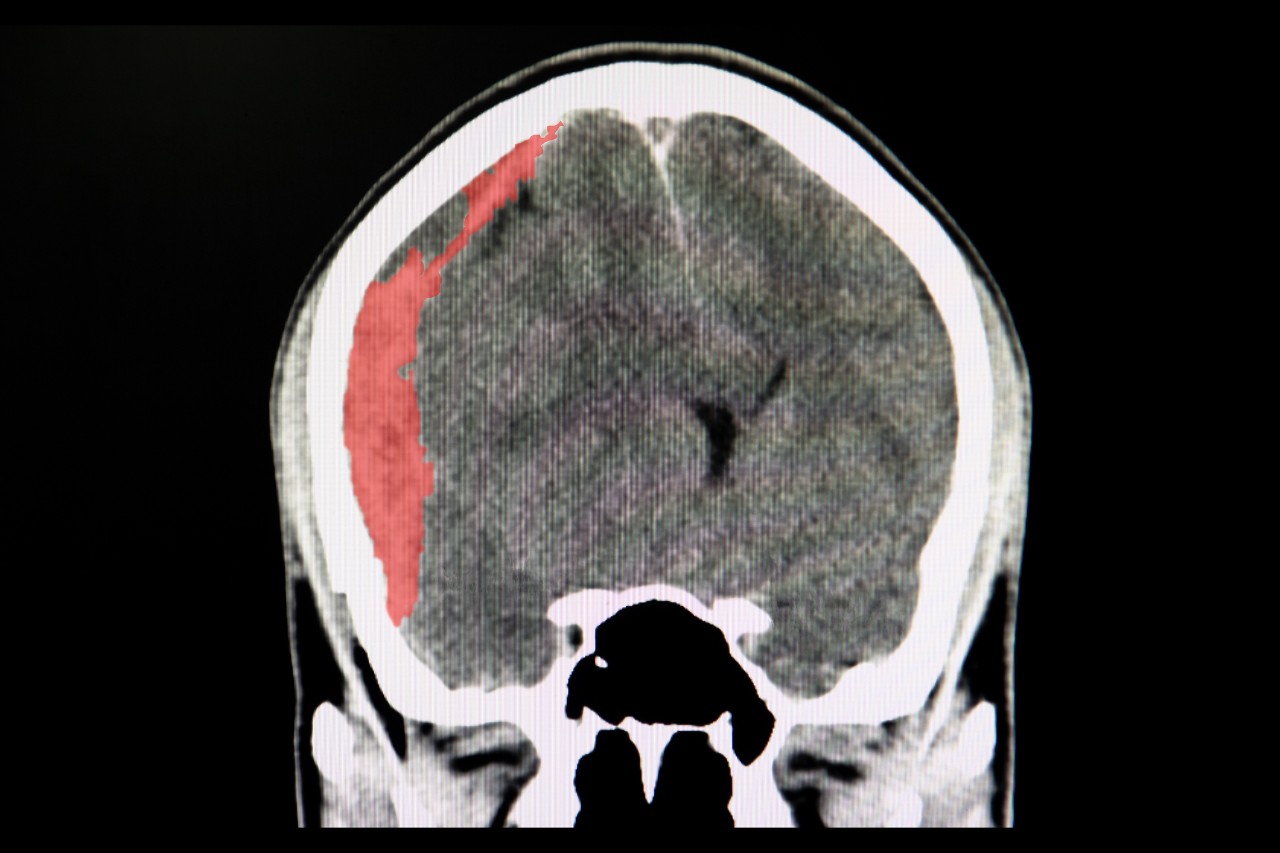

Up to half of all patients with subdural hematomas die or are severely disabled within one year of diagnosis. And although rates of this type of intracranial bleeding are rising in the American population, little research has focused on them.

Featured photo at top of a head CT scan displaying a subdural hematoma. Photo/Sopone Nawoot/iStock Photo.